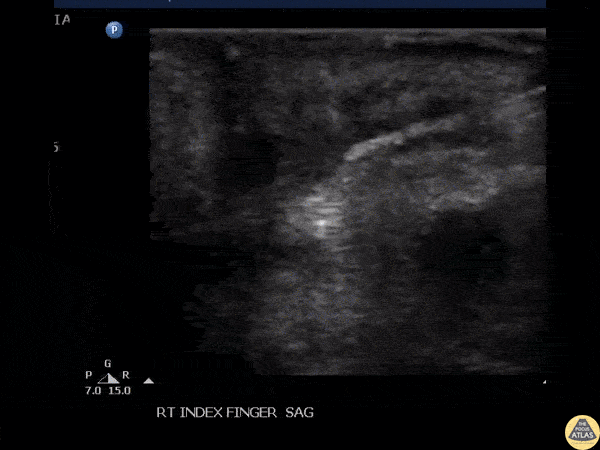

POCUS guided foreign body removal of a wooden splinter in the distal volar finger using alligator forceps. Image courtesy of Robert Jones DO, FACEP @RJonesSonoEM Director, Emergency Ultrasound; MetroHealth Medical Center; Professor, Case Western Reserve Medical School, Cleveland, OH View his original post here